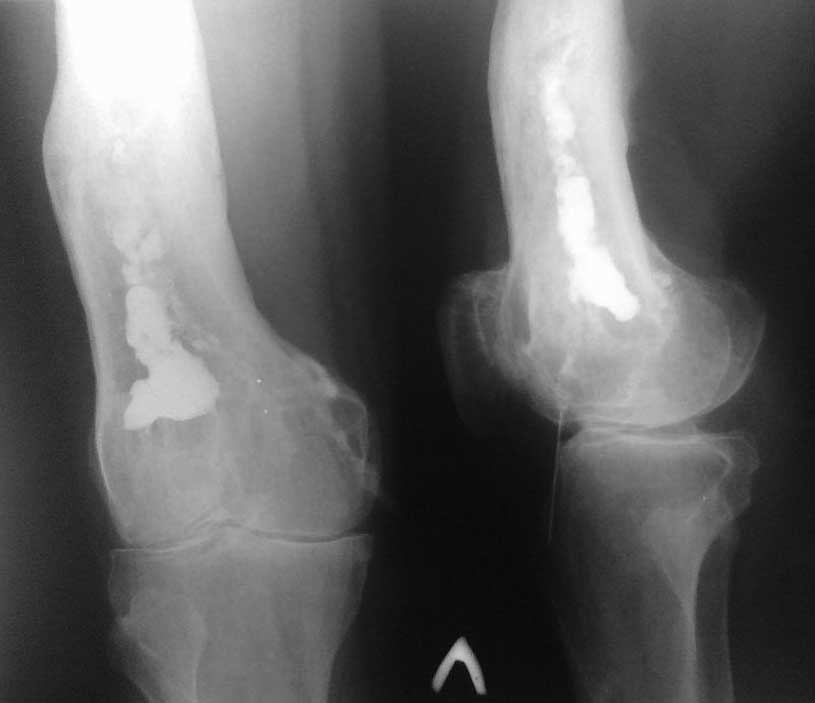

Уважаемые коллеги помогите определить с тактикой лечении. Больной Т 55 лет. Диагноз: Хронический посттравматический остеомиелит дистального метафиза левой бедренной кости, свищевая форма в стадии обострение, с остеодеструкции костной ткани.

Из анамнеза - в 1990 г. получил автодорожную травму. Лечился в ОКБ. Произведена операция - открытая репозиция. интрамед МОС н/3 бедренной кости 2-мя стержнями по Эндеру. Из за нагноение ран металлоконструкция удалена. Через 1 года появилась свищевая рана в н/3 бедра с гнойным отделяемым, с периодическими обострениями. В динамике инфицированная рана (свищ) периодический заживает вторичным натяжением. В 2011 году получал консервативное лечение в ГБ-4 г. Алматы. В данное время вышеуказанные жалобы беспокоят в течение 1 мес. Локально:При осмотре в н/3 левого бедра, область коленного сустава умеренно отечна. В области н/3 левого бедра по передне-латеральной поверхности имеется п/о рубец длиной 12 см, без признаков воспаления. По передне-медиальной поверхности в н/3 бедра имеется свищ 0,7х0,7 см с серозно-гнойным отделяемым. Определяется отечность, болезненность распирающего характера. Движения в коленном суставе (сгибания до160°) ограничено. Чувствительность и движение пальцев лев стопы не нарушены.